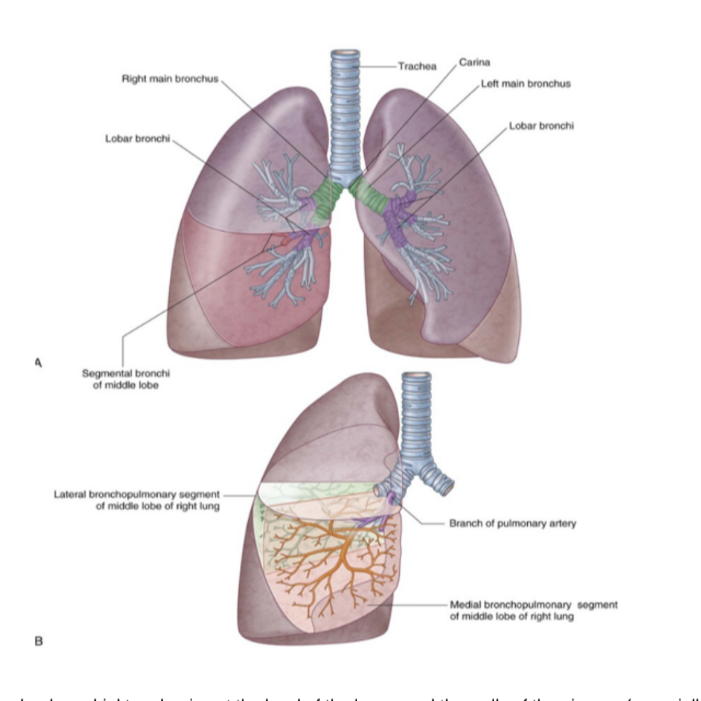

Bronchial tree —

Begins at level of larynx

Airway walls are supported by C-shaped rings of hyaline cartilage — trachea — flexible tube extending from vertebral level CVI in lower neck to vertebral level TIV/V in the mediastinum —

Here bifurcates into right & left main bronchus — can see the carina

In the lungs, the bronchi branch in a constant fashion to form branches of tracheobronchial tree

Branches of tracheobronchial tree

Each main bronchi divides into secondary bronchi

Each supplying a specific lobe of lung & dividing into several segmental bronchi to supply the segments

In each bronchopulmonary segment, the segmental bronchi give rise to multiple divisions — ultimately to bronchioles — which further subdivide & supply the respiratory surfaces

Bronchi walls are held open by discontinuous elongated plates of cartilage — not present in bronchioles

Lung/bronchopulmonary segments

Pyramidally shaped & are the largest subdivisions of a lobe with several important properties —

Apices face the lung root with their bases facing the pleural surface

Separated from adjacent segments by connective tissue septa

Supplied independently by a segmental bronchus & a tertiary branch of the pulmonary artery

Named according to segmental bronchi supplying them

Drained by intersegmental parts of the pulmonary veins lying in connective tissue between & drain adjacent segments

Can usually find 18-20 segments —

10 in right lung, 8-10 in left — dependent on combining of segments

Surgically resectable